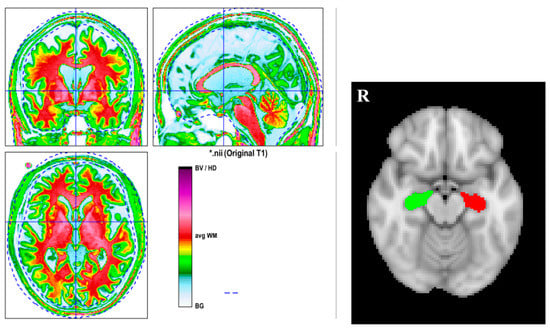

2.4. Volume Analysis

Reorigin was first conducted for the 3D T1-MPRAGE to make the following segmentation much more accurate with statistical parametric mapping, version 12 (SPM12), running on MATLAB R2020, version 9.8.0 (The MathWorks, Natick, MA, USA). Then, computational anatomy toolbox, version 12.6 (CAT12), was applied to the 3D T1-MPRAGE images to perform the brain segmentation for everyone separately. The segmentation quality was checked visually one by one. Figure 1 displays the segmentation result of one subject. Brain volumes (GM, WM, and total intracranial volume (TIV)) can be obtained automatically. By using the function “extracting ROI data” in CAT12, the volume of the bilateral hippocampus for each participant can be obtained.

Figure 1.

The left side figure is the segmentation result of a subject. The right side figure is the hippocampal ROI from CAT12. The computational anatomy toolbox, version 12.6 (CAT12), was applied to 3D T1-MPRAGE images to perform the brain segmentation. BG = background, CSF = cerebrospinal fluid, CGM = cortical GM, GM = grey matter, WM = white matter. The red color indicates WM; the green color denotes GM; and the yellow color represents the interface between WM and GM. * just represents the name of the subjects.